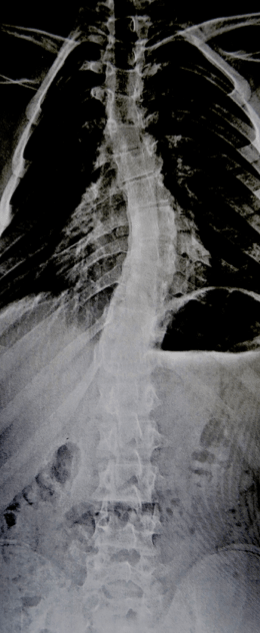

la scoliose

elle est suspecte quand elle survient chez le garçon, d’évolution rapide, avec une gibbosité gauche, et quand elle est douloureuse. la radio standard peut montrer un écartement des pédicules des vertèbres.